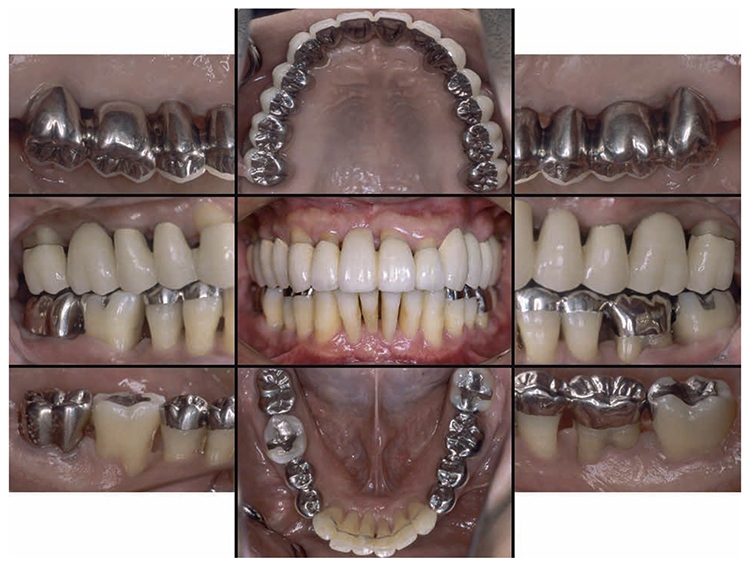

At reevaluation testing after basic periodontal treatment, the color of gingiva improved to pink, and findings showed that inflammation in the marginal gingiva with primarily blood congestion had subsided. Class 4 gingival recession (Miller’s gingival recession classification) was observed on the entire jaw. (Fig.3a). The average PD of the entire jaw was 2.8mm, maximum PD was 10.0mm, the ratio of PD of 3mm or below was 84.0%, PD of 4-6mm was 12.5%, PD of 7mm or above was 3.5% and BOP rate improved to 11.8%. However, PD of 7mm remained on 17, 10.0mm on 27, 5.0mm on 36, and 7.0mm on 46. Additionally grade 1 furcation involvement remained on the buckle and lingual side of 36, mesial distal direction on the buckle side of 17, grade 2 on the buckle side of 27. Teeth mobility was grade 1 on 44 and 46 (Fig.3b). X-ray findings showed that dental calculus was removed from the gingival margin on the maxilla and mandible. Despite the clearly visible alveolar hard line, no improvement was shown on the alveolar bone. (Fig.3c).

Fig 3a

(Fig.3a) Intraoral photo after completion of basic periodontal treatment has completed (2010.1)

6) Prosthetic treatment

After orthodontic treatment was completed, fabrication of the final prosthesis was started.. Preliminary impression of the maxilla and mandible were taken, anatomic facebow and checkbite were obtained, and prosthetic diagnosis was performed. In the treatment plan before surgery, the first choice for the maxilla was the full mouth bridge that connects all teeth. However, since no parallelism was seen on the anchor teeth, and additionally all teeth were vital teeth, convenient pulpectomy was sought as a possibility. Additionally, in designing treatment for patients with severe periodontitis, to disperse the occlusal load to the entire jaw, which was most important, semi-fixed multi-tooth prosthetic using key and keyway attachment was designed for final prosthetic in this case. After taking parallelism of anchor teeth into consideration, multi-tooth models with attachments were designed for 13 and 14, and for 22 and 23. After deciding on the shape of prosthetics, anchor teeth were formed, impression was taken, and subsequently final confirmation was made on accurate fit with coping trial. After final prosthetic treatment on the maxilla, prosthetics were placed on the mandible starting with 47. Since metal crowns were placed on both 47 and 36, onlay-type metal crowns were placed on 44, 45, 34 and 35 for occlusal support. After completion of prosthetic treatment on all teeth, confirmation was made with an occlusal force tester (Dental Prescale®,GC, Tokyo) that occlusal force was equally distributed across the entire jaw. Additionally, nighttime bruxism was addressed by producing and applying nightguards since the patient had the habit of clenching.

7) Reevaluation testing (December 2003)

At the reevaluation examination after treatment to restore oral function, the color of gingiva was pink, and with prosthetics, intraoral harmony was replicated esthetically and functionally. (Fig.6a). The average PD across the entire jaw was 2.1mm, maximum PD was 4.0mm, the ratio of PD of 3mm or below was 99.3%, no BOP was found and the condition of the periodontal tissue was stable (Fig.6b). In the X-ray, continuity of the alveolar hard line was replicated and the sequence of bone trabeculae was normal, and therefore, the patient transitioned to the SPT phase (Fig.6c).

Fig 6a

(Fig.6a) Intraoral photo after completion of restoration of oral function was completed(2013.4)